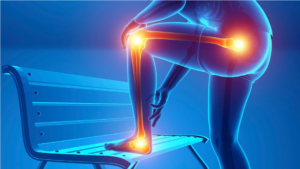

Affûtez votre analyse des douleurs du membre inférieur et orientez vos patients vers l’orthèse la plus adaptée pour un conseil expert et sécurisant au comptoir.